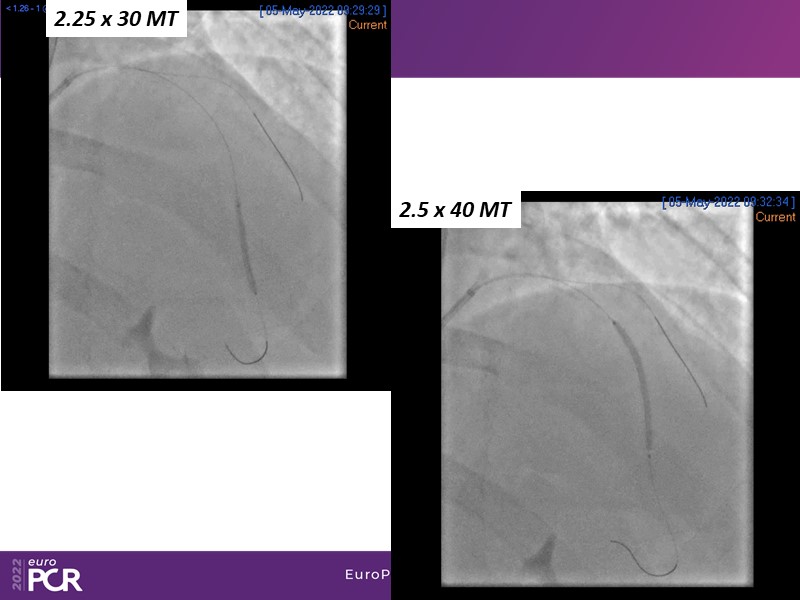

- To find out more about the application and mechanism of a sirolimus coated balloon for coronary artery disease treatment with case presentations in complex settings

- To understand how useful is a DES and DCB stent platform in complex coronary artery disease settings with case demonstrations and follow-up in diabetes mellitus